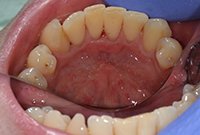

Снятие твердых зубных отложений ультразвуком

Удаление твердых зубных отложений ультразвуковой насадкой у девушки 27 лет.

Снятие твердых зубных отложений ультразвуком До

Снятие твердых зубных отложений ультразвуком После